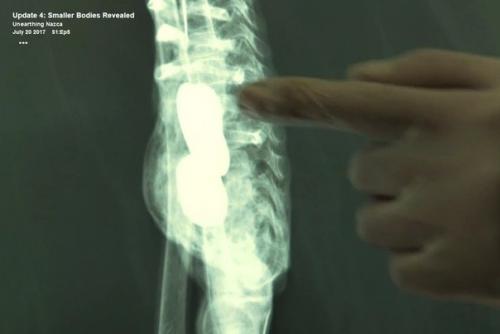

Место, где Марио обнаружил два саркофага, до сих пор держится в секрете. Марио сообщил, что в одном из саркофагов находились только предметы, а во втором - два тела среднего размера и множество маленьких тел. Большое тело было найдено вне саркофага.